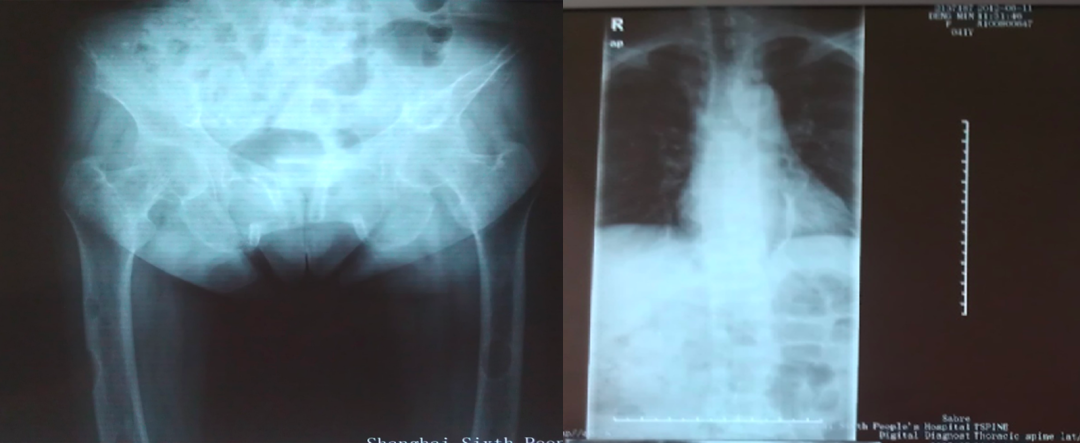

病例4:

男性,82岁。

主诉:腰痛1年。

实验室检查:BMD(L1-4 T值 4.7、SDNECK T值 0.1SD)。

诊断:前列腺癌、骨转移。

5、高BMD、ALP高可能为前列腺癌、畸形性骨炎、骨纤维异样增殖症等疾病;